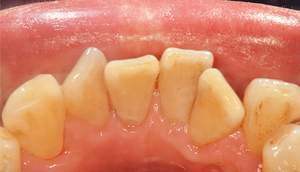

歯石除去

治療前

治療後

| 年齢 | 25歳・男性 |

| 主訴 | 歯石をとりたい・検診 |

| 治療内容 | 各種検査・歯石除去 |

| 治療期間 | 60分 |

| 費用 | 初診料3,000〜4,000円前後 +歯石除去約1,000円 |

| リスク・副作用 | ・処置後に歯がしみることがあります。 ・歯と歯の間に隙間ができるので、息が漏れ発音しにくいと感じることがあります。 ・歯ぐきの炎症が軽減すると歯ぐきが引き締まり、歯が長く見えることがあります。 |

| 担当者所見 | 前歯の裏側にすぐに歯石が溜まってしまいザラザラして気になるとご相談いただいたので適切な歯ブラシの当て方とフロスの通し方をお伝えさせて頂きました。 |